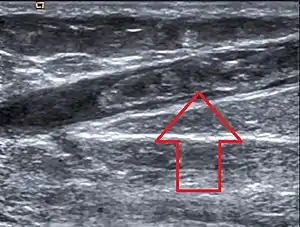

| Ultrasonographic image showing thrombosis of the great saphenous vein. | |

Risk factors include deceased mobility, recent surgery, pregnancy, birth control pills, cancer, obesity, varicose veins, family history, and at site of an intravenous insertion.[2][1] The underlying mechanism may involve poor blood flow, increased blood clotting, and damage to a vein.[1] Diagnosis is generally by ultrasound.[2]